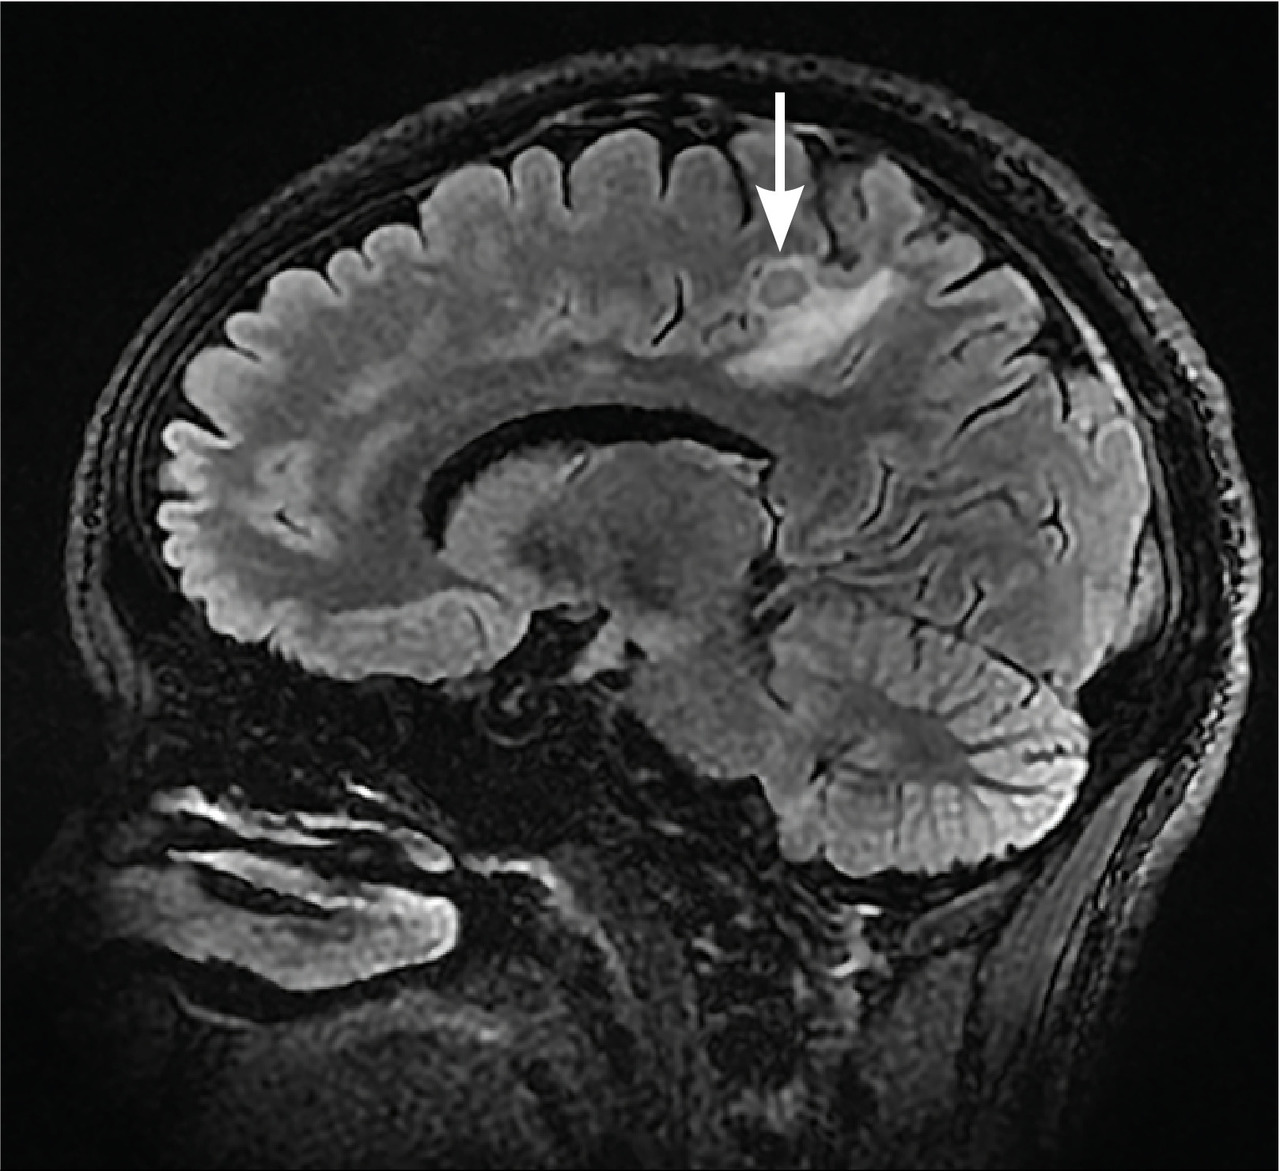

L’imagerie montrait : sur la tomodensitométrie (TDM) thoracique une miliaire tuberculeuse pulmonaire et des adénopathies médiastinales ; sur l’imagerie par résonance magnétique (IRM) du rachis une spondylodiscite T11-T12 (fig. 1 ) ; sur la TDM abdominale des abcès paravertébraux de T9 à T12 le long des psoas (fig. 2 , flèches blanches) et des lésions micronodulaires hépatiques multiples (fig. 2 , flèche jaune) ; sur l’IRM myocardique des signes de péricardite (fig. 3 , flèches). La ponction lombaire montrait une méningite. Un tuberculome était visible sur l’IRM cérébrale, entouré d’un œdème périlésionnel (fig. 4 ). Le diagnostic de tuberculose disséminée était prouvé par polymerase chain reaction sur une ponction d’abcès. Compte tenu de l’atteinte neuroméningée, un traitement adjuvant par corticothérapie s’imposait dans le cas présent, de même qu’une antibiothérapie de 9 à 12 mois.1

L’imagerie montrait : sur la tomodensitométrie (TDM) thoracique une miliaire tuberculeuse pulmonaire et des adénopathies médiastinales ; sur l’imagerie par résonance magnétique (IRM) du rachis une spondylodiscite T11-T12 (